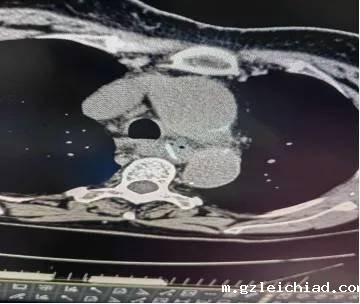

了解情况后,程医生立即向内镜中心主任郭庆涛汇报,告知了张老太儿子食管异物的风险,很可能食管已经“扎穿”了,如果穿孔较大可能要外科手术的,甚至有生命危险,张老太儿子李先生也十分配合,希望尽快取出。郭庆涛立即联系了神经内科、胸外科会诊,并急诊做胸部CT。

CT考虑已经出现食管穿孔